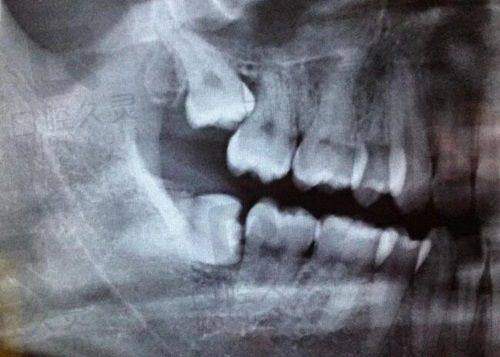

精良的医疗设备保护。门诊部引进了一系列精良的口腔医疗设备,如口腔CT、数字化牙片机等。这些设备能够为医生提供更正确的诊断依据。以口腔CT为例,它可以清晰地显示牙齿、牙槽骨等口腔内部结构,帮助医生更精细地判断病情。在种植牙手术中,医生通过口腔CT了解患者牙槽骨的密度、高度等情况,从而选择合适的种植体,提高种植牙的成功几率。患者们对门诊部的精良设备也给予了高度评价,认为精良的设备让他们在就诊时更有信心。